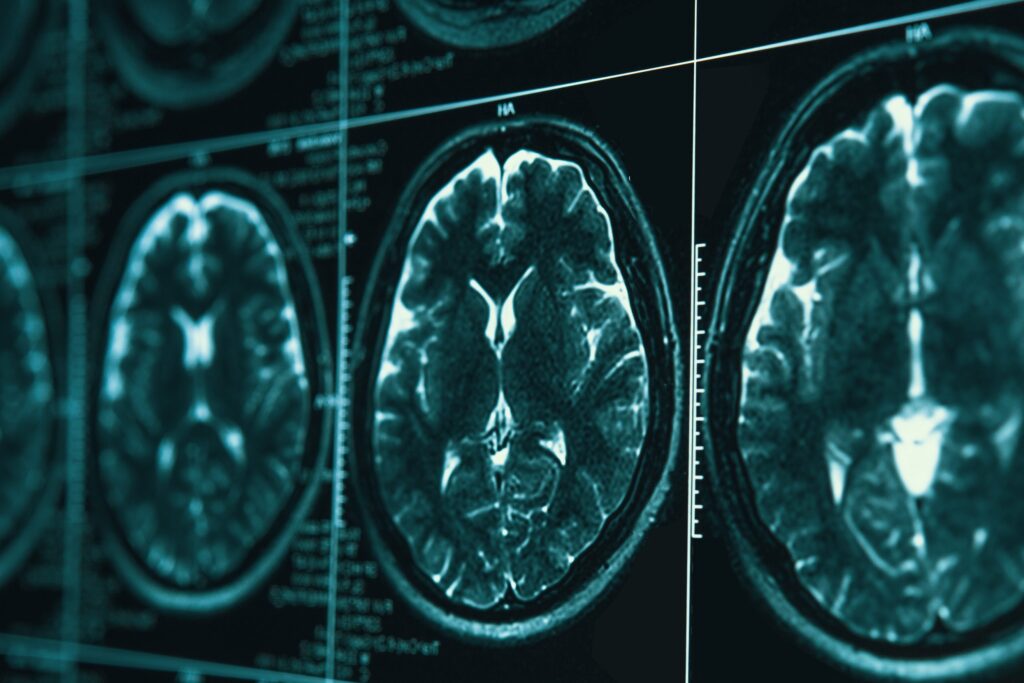

Any long-term effects of TBI will depend on which area of the brain experienced the most trauma. The frontal lobe or forehead area of the brain is what regulates reasoning, problem solving, judgement, impulse control, and planning, so a traumatic brain injury there would potentially cause the individual to engage in riskier or inappropriate behavior. An injury to the left side of the brain may lead to issues with logic, speech difficulties, or trouble understanding others. Injuries to the right side of the brain can cause problems processing visual information, neglect, or hinder the ability to perform familiar tasks, known as apraxia.